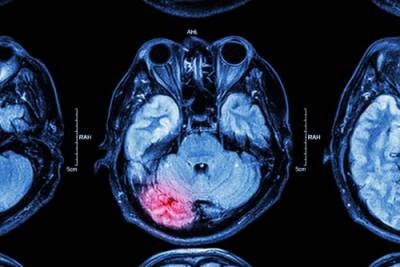

Trauma to the head sustained in a fall accident, car crash, or other traumatic events can damage the brain. Our brains control everything from physical movement to emotions and cognition. Consequently, traumatic brain injuries (TBI) can have a profound effect on the sufferers. The physical pain of a brain injury may eventually fade, but many TBI victims are left with cognitive impairment or psychological problems long after the visible injuries have healed. These problems can make it difficult if not impossible to work or carry out everyday tasks. If you or a loved one experienced a traumatic brain injury, it is important to explore your legal options.

Traumatic brain injury is one of the most dangerous types of injuries a person can suffer. TBIs not only cause physical problems like headaches and vertigo, but may also cause mental, cognitive, and psychological problems.